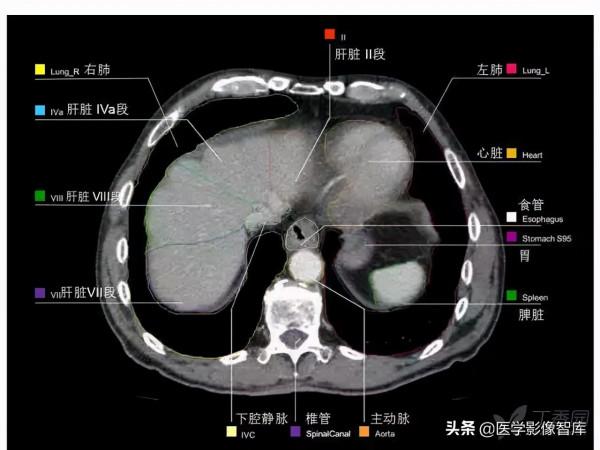

第十四層:肝靜脈水平

1. Intercostal muscle 肋間肌

2. Rib 肋骨

3. External oblique muscle 腹外肌

4. Right hepatic vein 肝右靜脈

5. Inferior vena cava 下腔靜脈

6. Left hepatic vein 肝左靜脈

7. Diaphragm 膈肌

8. Vagus nerve 迷走神經

9. Esophagus 食管

10. Liver (left lobe) 肝左葉

11. Rectus abdominis muscle 腹直肌

12. Stomach 胃

13. Left lung 左肺

心臟